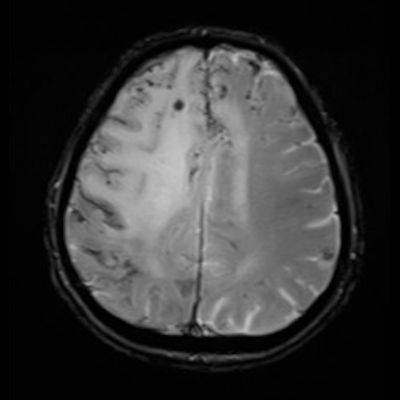

- A) Aksiyel planda FLAIR sekansta asimetrik kortiko-subkortikal vazojenik ödemi düşündüren yüksek sinyalli hafif ekspansil lezyonlar (turuncu ok).

- B) ADC haritasında kolaylaşmış difüzyon (mavi ok).

- C) Gradient seride milimetrik hemosiderin kalıntıları ve süperfisyal siderozis (kırmızı ok)

- D) Kontrastlı T1A sekansta hafif leptomeningeal boyanma (sarı ok).